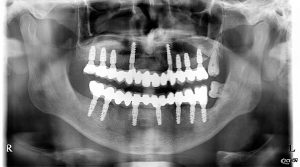

Prezentowany przypadek leczenia implantoprotetycznego wymagał wiele uwagi. Zaawansowana periodontopatia oraz protruzja obuszczękowa wymagała ekstrakcji prawie wszystkich zębów. Zaplanowano leczenie protezą stałą wspartą na wszczepach śródkostnych. Wprowadzenie wszczepów w szczęce wymagało podniesienia dna zatoki szczękowej prawej. Praca oparta na łącznikach typu MultiUnit frezowana z tytanu licowana ceramiką. Pacjent odzyskał swój uśmiech z lat młodości.

Lek. dent. Maciej Kwiatkowski – leczenie implantoprotetyczne